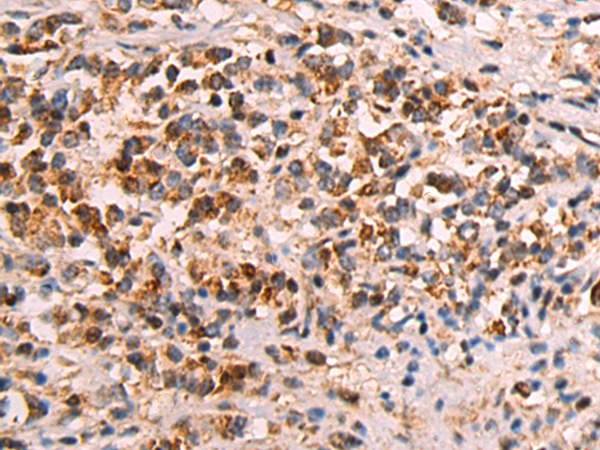

ELISA, WB, IHC

IHC positive control:

Human gastric cancer and Human tonsil

IHC Recommend dilution:

50-200